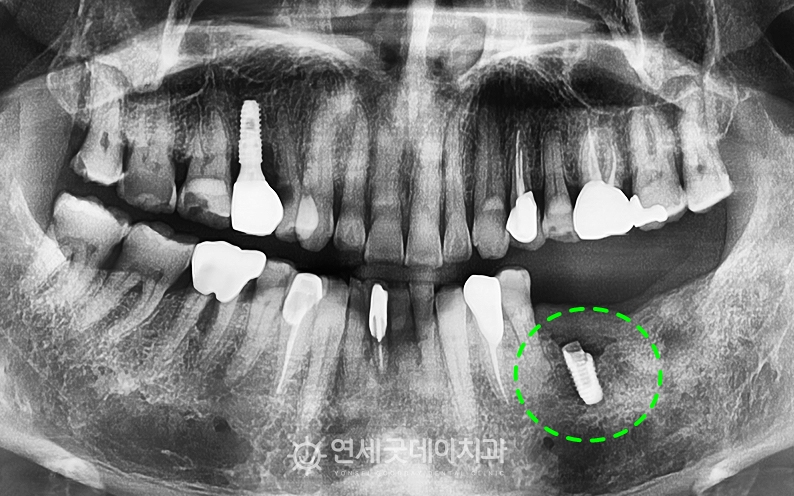

임플란트 재수술(i-Reset) 치료전후, 60대 남성

임플란트 재수술 치료전후 – 50대 남성